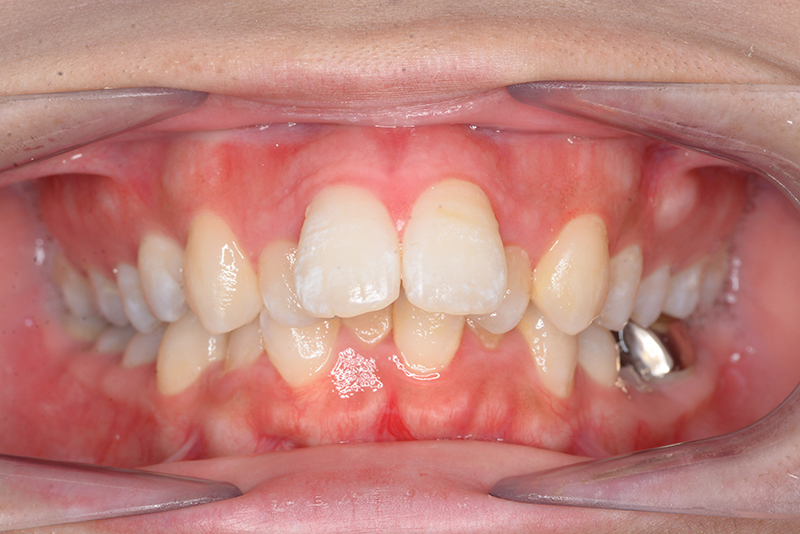

初診時

FP・IOP

主訴 出っ歯 診断名 アングルⅡ級2類

初診時年齢 24歳11ヵ月 性別 動的治療期間 20ヵ月

顔貌所見 正貌はほぼ対象。側貌はconvex type、著しい口唇閉鎖不全が認められた。

口腔内所見 over jet 11.5mm、over bite 5.5mm、右側臼歯関係Full ClassⅡ級、左側end onⅡ級、上顎顎歯列はテーパー型であり、上顎中切歯は押し出されるように大きく唇側傾斜していた。下顎前歯部は叢生を呈しており、左下5は歯冠長が短く半埋伏していた。